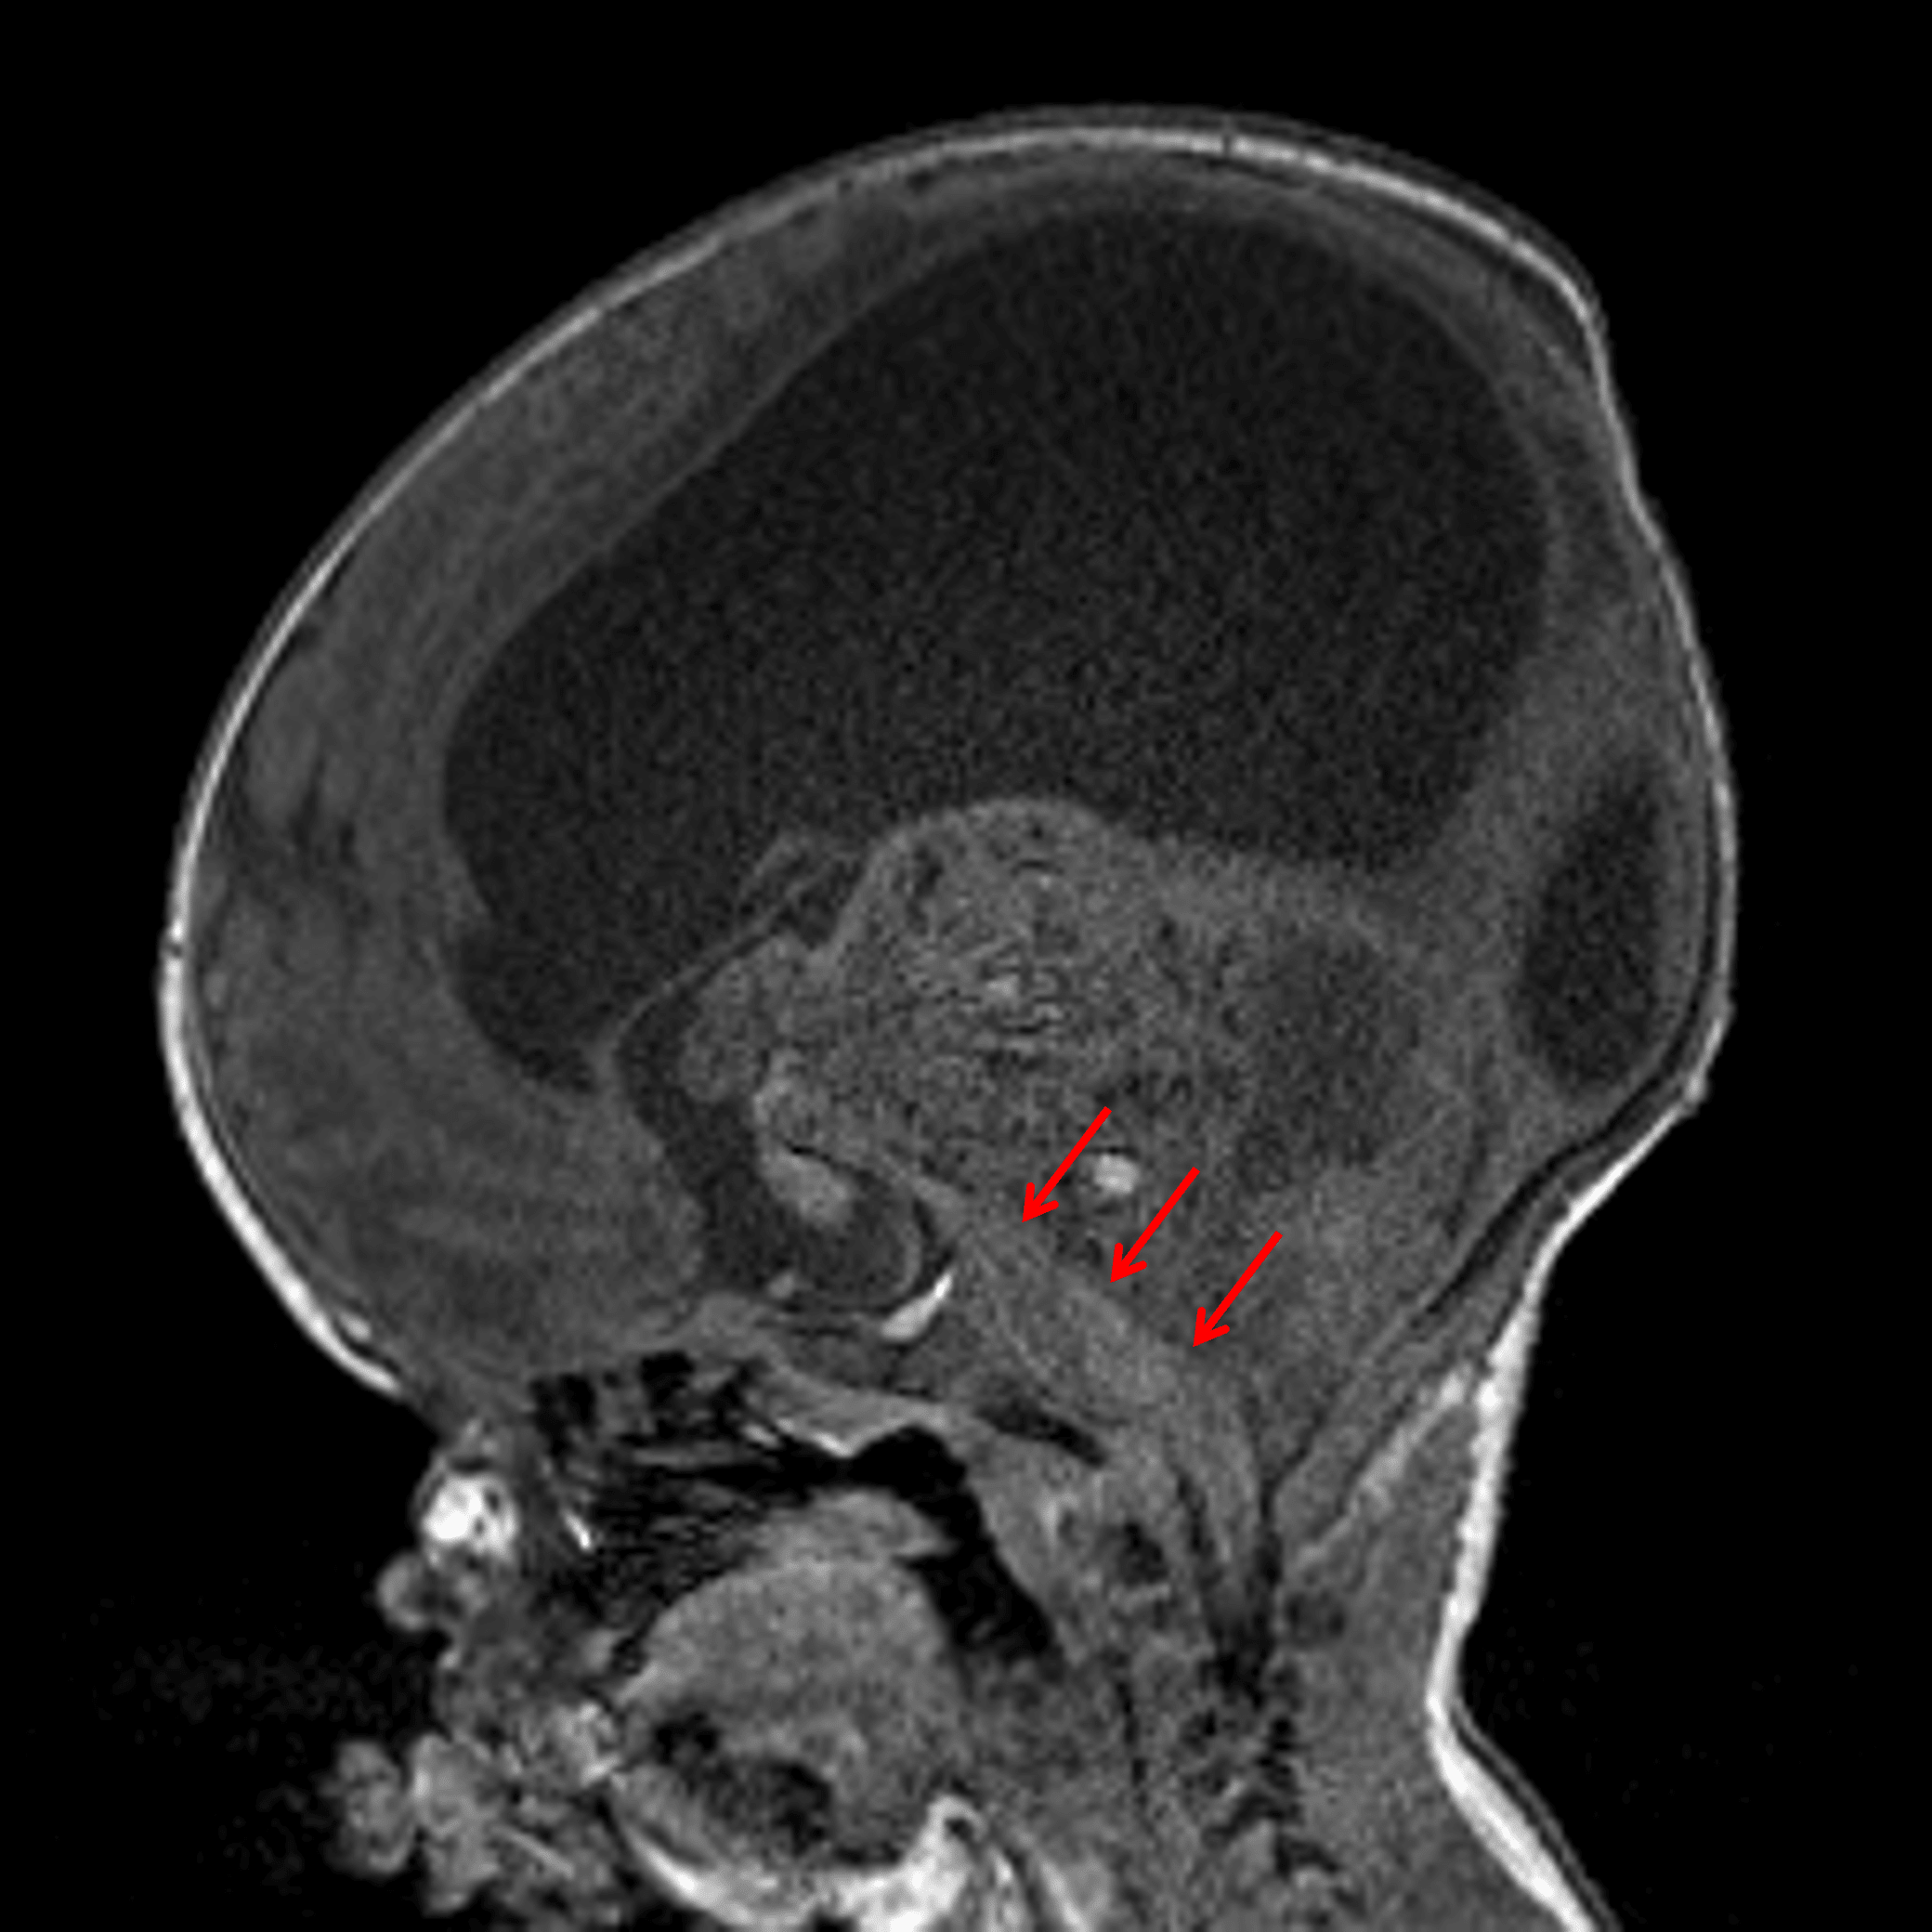

Large mass centered in the superior aspect of the posterior fossa with anterior displacement of and severe mass effect on the brainstem (red arrows).